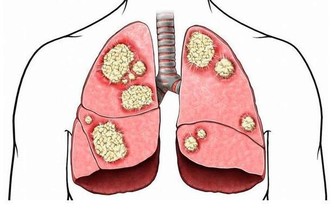

抗生素

抗生素並非不是好藥,只是現在有些濫用。抗生素,包括口服藥,輸液、打針藥,藥物本身即損傷陽氣。尤其冬季輸液更傷陽氣,室外溫度本來就低,遠遠低於體溫,寒涼的藥液滴入血管內,陰寒隨之進入內臟,需要人體陽氣去溫煦氣化,這樣就可能導致傷陽太甚。

經常吃的4類藥物,正在損傷你的陽氣!

因此,在冬天不得不輸液時,醫生完全可用先溫水適當加溫抗生素,根本不會影響藥效,

且可大大減少體內陽氣的消耗,病患也可弄個小棉襖套住藥液瓶以保溫。